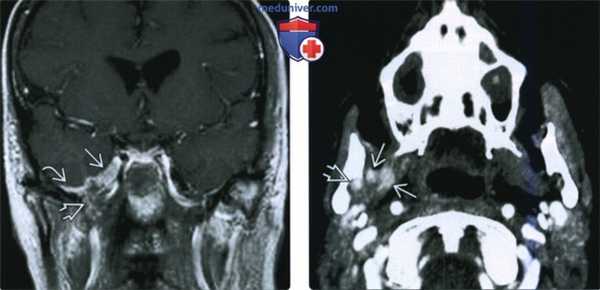

(Слева) МРТ Т1ВИ с КУ, коронарная проекция, этот же пациент. По нижнечелюстному нерву опухоль распространяется в овальное отверстие и тройничную полость. Также опухоль прорастает латеральнее, в твердую мозговую оболочку средней черепной ямки.

(Справа) КТ с КУ в аксиальной проекции, этот же пациент. В области правого отверстия нижней челюсти определяется накапливающая контраст опухоль. В жевательном пространстве видны участки аномального накопления контраста вдоль волокон нижнечелюстного нерва.